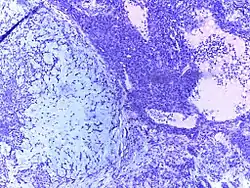

![]() | Dysgerminoma | Dysgerminoma characterized by uniform cells resembling primordial germ cells separated by fibrous septa with lymphocytes. | Category: Histopathology of ovarian dysgerminoma | Ovarian dysgerminoma |